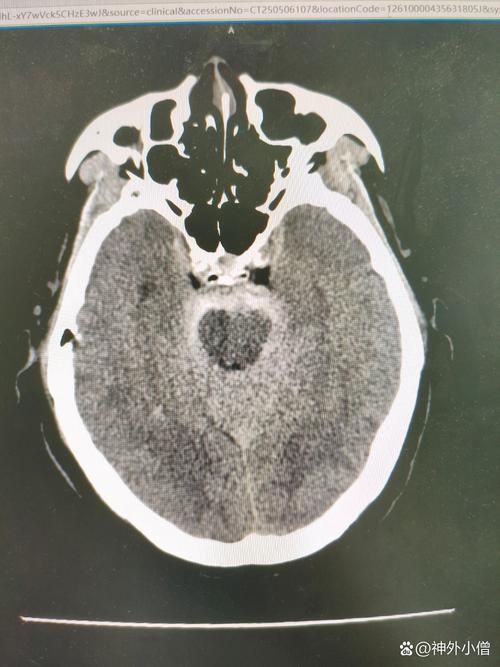

(图片来源网络,侵删)

(图片来源网络,侵删)- 头颈CTA或MRA: 看看大血管有没有明显的狭窄或闭塞。